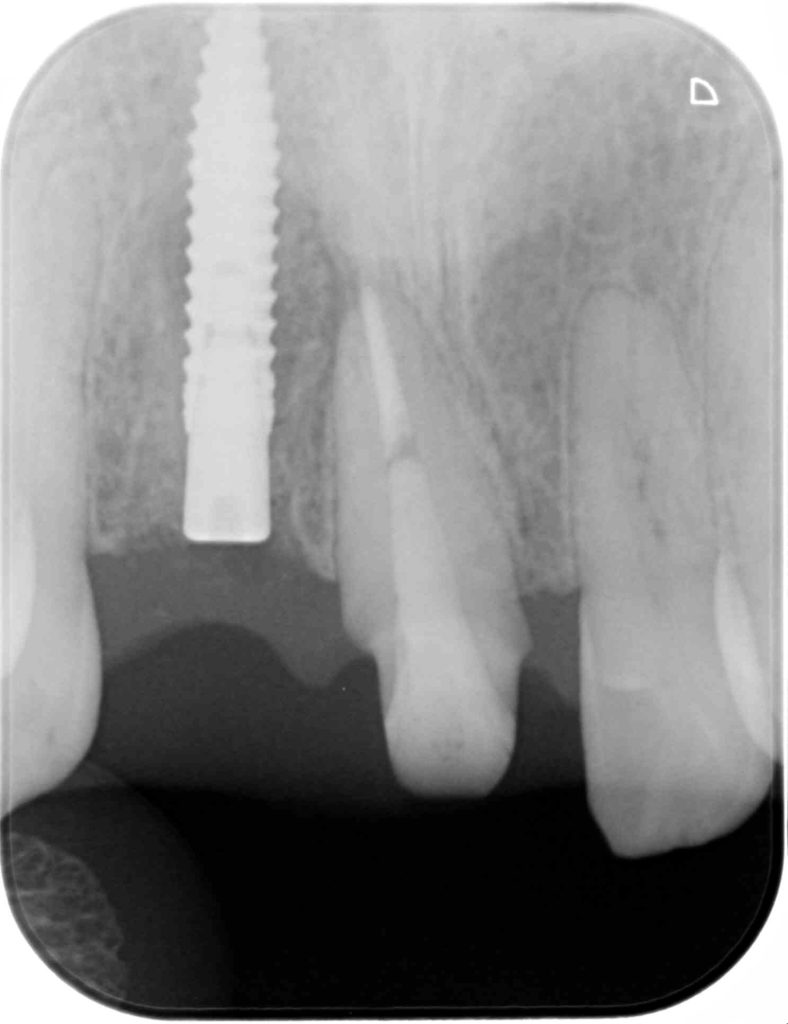

下記の症例は前歯部のインプラント治療において、骨、歯肉の造成をインプラント埋入と同時に行いました。

エビデンスでは抜歯後に唇側骨が吸収していく為、抜歯と同時にインプラント埋入し、非吸収性の骨補填材を充填し、その移植した骨の吸収を最小限に留めておく為に歯肉の厚みが必要です。その歯肉の厚みを確保する為に結合組織を採取しました。